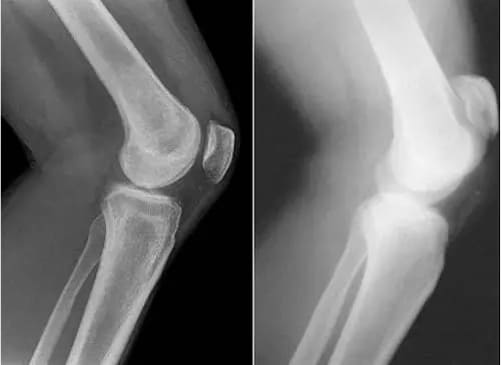

Вы только посмотрите на рентген суставов до и после использования «Сусталита»:

Восстановление локтевого сустава. Пациент, 31 год.

Продолжительность курса средства «Сусталит»: 2 месяца.

Его сустав полностью восстановился.